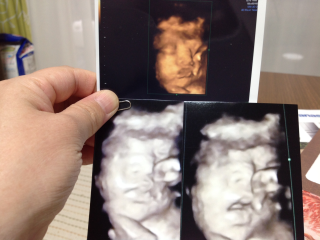

なかなかいつも顔を隠してばかりで今回も先生粘ってくれました(´・∀・`) だんだん目は旦那似かな? 鼻は私似かな?とか言いあってます(*´∀`*)

なかなか見れない週数に入りお顔を久々に見せてくれました!! 大きさは1860g程度、平均の大きさの女の子です。前回よりもお肉がついて赤ちゃんらしくなってきました。厚ぼったい唇は私に似ています。 目鼻立ちもしっかりしていると言われました!早く会いたくて仕方ないです。